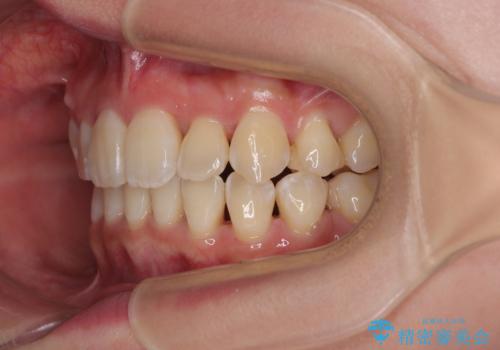

- 前歯1本が後ろ側に隠れてしまうほどのデコボコを気にして来院された患者様です。

前歯のデコボコが顕著なのはもちろんですが、左右ともに奥歯の咬み合わせに問題があり、上顎臼歯が前方位にある状態でした。